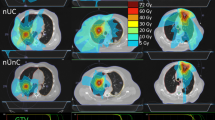

The 0-view method increased V5 of the combined lung by 5% compared to the 2-view technique for UL tumours (p value = 0.04), 9.5% for ML (p value = 0.04), and 16.8% for LL tumours (p value = 0.04). In contrast to all other techniques, for UL, ML, and LL tumours, lung volume parameters V5, V10, V20, and V30 for the 0-view technology were consistently higher. V5 was less in DIBH technique than the 2-view technique for ML tumours by 4.2%. In comparison with other techniques shown in Fig. 2, the volume parameters V10, V20 andV30 were constantly lower in DIBH technology.

The observed maximum mean lung dose (MLD) was 6.2 Gy ± 2.7 Gy with a 0-view technique and the minimum was 3.85 Gy ± 1.75 Gy with the DIBH technique as shown in Fig. 3. The difference in MLD between DIBH and 2-view was negligible (p-value = 0.67). For LL tumours, the MLD increased from 4 to 6.5 Gy from the 2-view to 0-view technique (p-value = 0.009) (Fig. 3). Except for 0-view and 1-view, the difference in MLD was not significant for ML and UL tumours. (p-value > 0.11).

As shown in Fig. 4, for a tumour in the LL of the lung, the 5 Gy volume (V5Gy) for contralateral lung was minimal with Cyberknife plans than HT and VMAT plans. This increase in HT and VMAT plans could be due to the beam entry through the opposite lung. During helical and arc therapy, the beam entry through the opposite lung was unavoidable. The 5 Gy dose volume in the ipsilateral lung was higher in Cyberknife than HT and VMAT plans. In Cyberknife, the optimizer restricts the beam entry through the contralateral side due to the reduced clearance between the patient surfaces to the machine to avoid a collision. This reduces the degrees of freedom of the optimizer resulting increased 5 Gy volume in the ipsilateral lung.